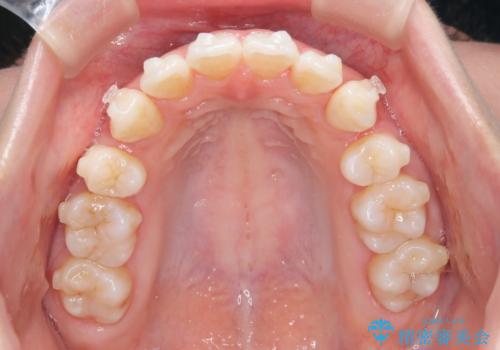

【抜歯インビザ】凸凹を綺麗になおしたい

- 前歯の凸凹を主訴に来院されました。

叢生量が多いため、抜歯が必要となるため、ワイヤー矯正をお勧めしましたが、患者さんの希望によりインビザラインで治療を開始しました。途中でワイヤーリカバリーを必要とせず終了でき患者さんには満足していただけました。